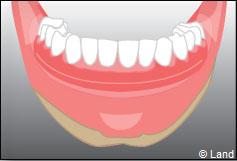

Exemple d’une réhabilitation complète implantaire